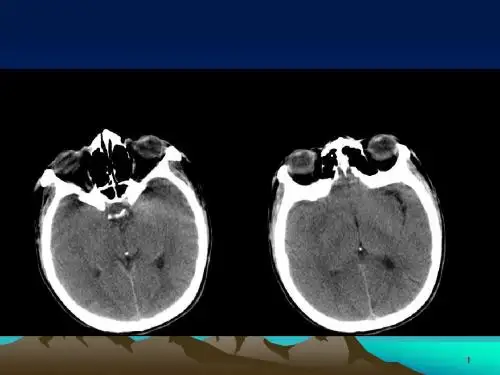

分析松果体区肿瘤的CT表现,诊断提供帮助。

松果体区可见一类圆形软组织肿块,边界清晰,密度均匀,其内可见点片状钙化影。

头颅CT扫描、核磁共振检查可发现肿瘤并做定位诊断。

松果体钙化移位:松果体钙化常见于成人,且随年龄增加而更易出现,约75%正常成人在CT扫描时显示有松果体钙化。

其直径

范围通常为3~5mm,但有时可能会更广泛些。

松果体钙化面积大,移位,出现在小儿身上,则应考虑到是否有松果体区肿瘤的可能性。